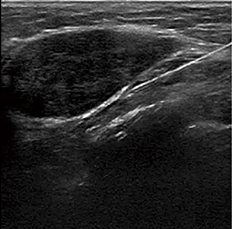

●BEAM(Biopsy Enhancement Auto Mode)

穿刺を行う際に,針を見やすくする技術です。Bモード画質を劣化させることなく,針の映像化にとって最適な送受信を実現することにより,細い針でも強調表示することが可能です(図4,5)。

図4 針強調オフ |

| (図4,5画像ご提供:ちば県民保健予防財団・橋本秀行先生) | |